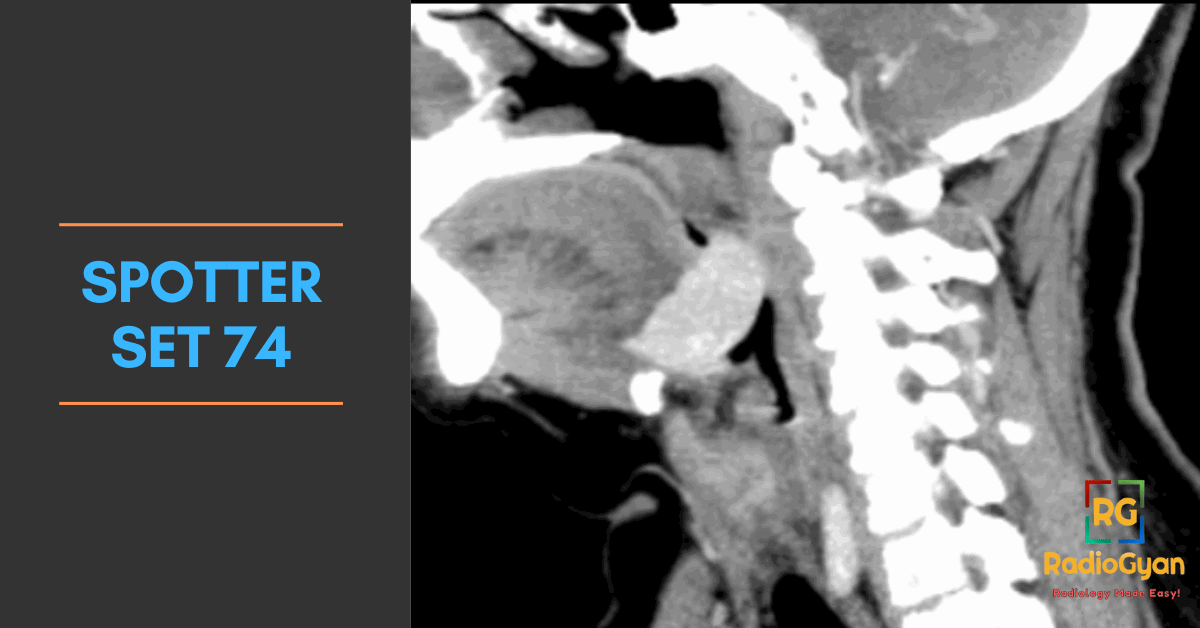

Explore high-yield radiology spotters with detailed explanations and case discussions to enhance your diagnostic skills at RadioGyan.com.